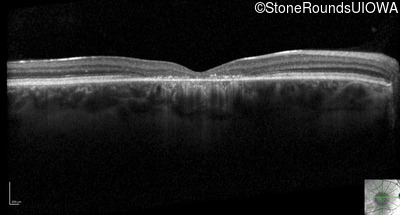

Optical Coherence Tomography - Left - 20/200

Exemplar / OCT Stack